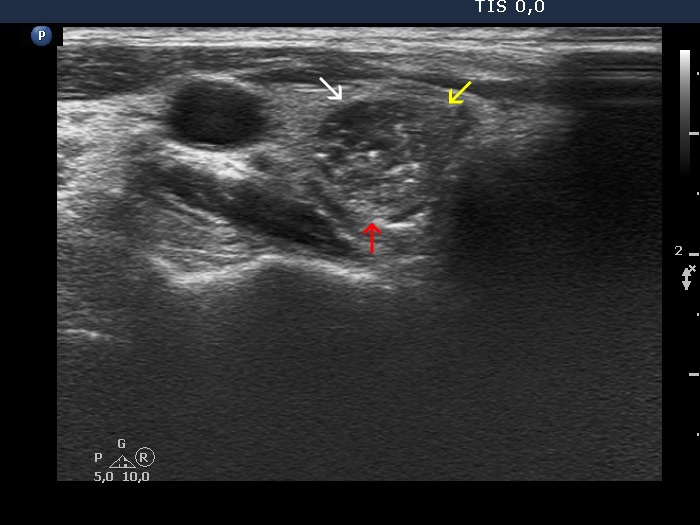

The echogenicity of the nodule - case 2166 (ultrasonographic picture 5b)

Lower part of the right lobe, transverse view. This nodule is heterogeneous because it is composed of deeply (white arrow), minimally (yellow arrow) hypoechoic and echonormal (red arrow) parts.